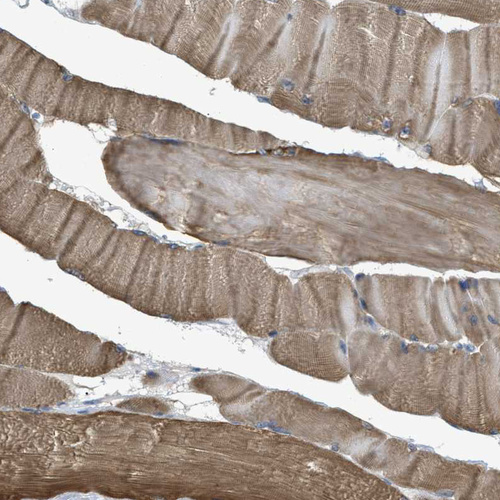

Immunohistochemical staining of human cerebellum, prostate, skeletal muscle and skin using Anti-BAG3 antibody HPA020586 (A) shows similar protein distribution across tissues to independent antibody HPA018493 (B).